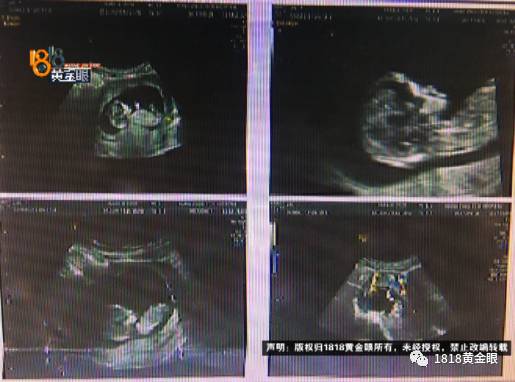

小李是河南人,到杭州打拼四五年了。大约是14年的时候,经朋友介绍认识了小傅,两人很快确立了恋爱关系。今年6月左右,小李怀上了孩子。9月中旬两人一起去医院做孕期检查,据小李说,从那之后小傅对她的态度就发生了转变。

小李:“第一次是我们自己怀孕了,但是我们都不知道,后来去北京旅游了,太累了,回来又还人家班,小孩子就没有了。过了一两个月,我们就去做了人工受精。上班的时候肚子特别痛,上不了,然后给我送到医院,发现是宫外孕。”

小李说,之前的经历让她格外珍惜这个孩子。